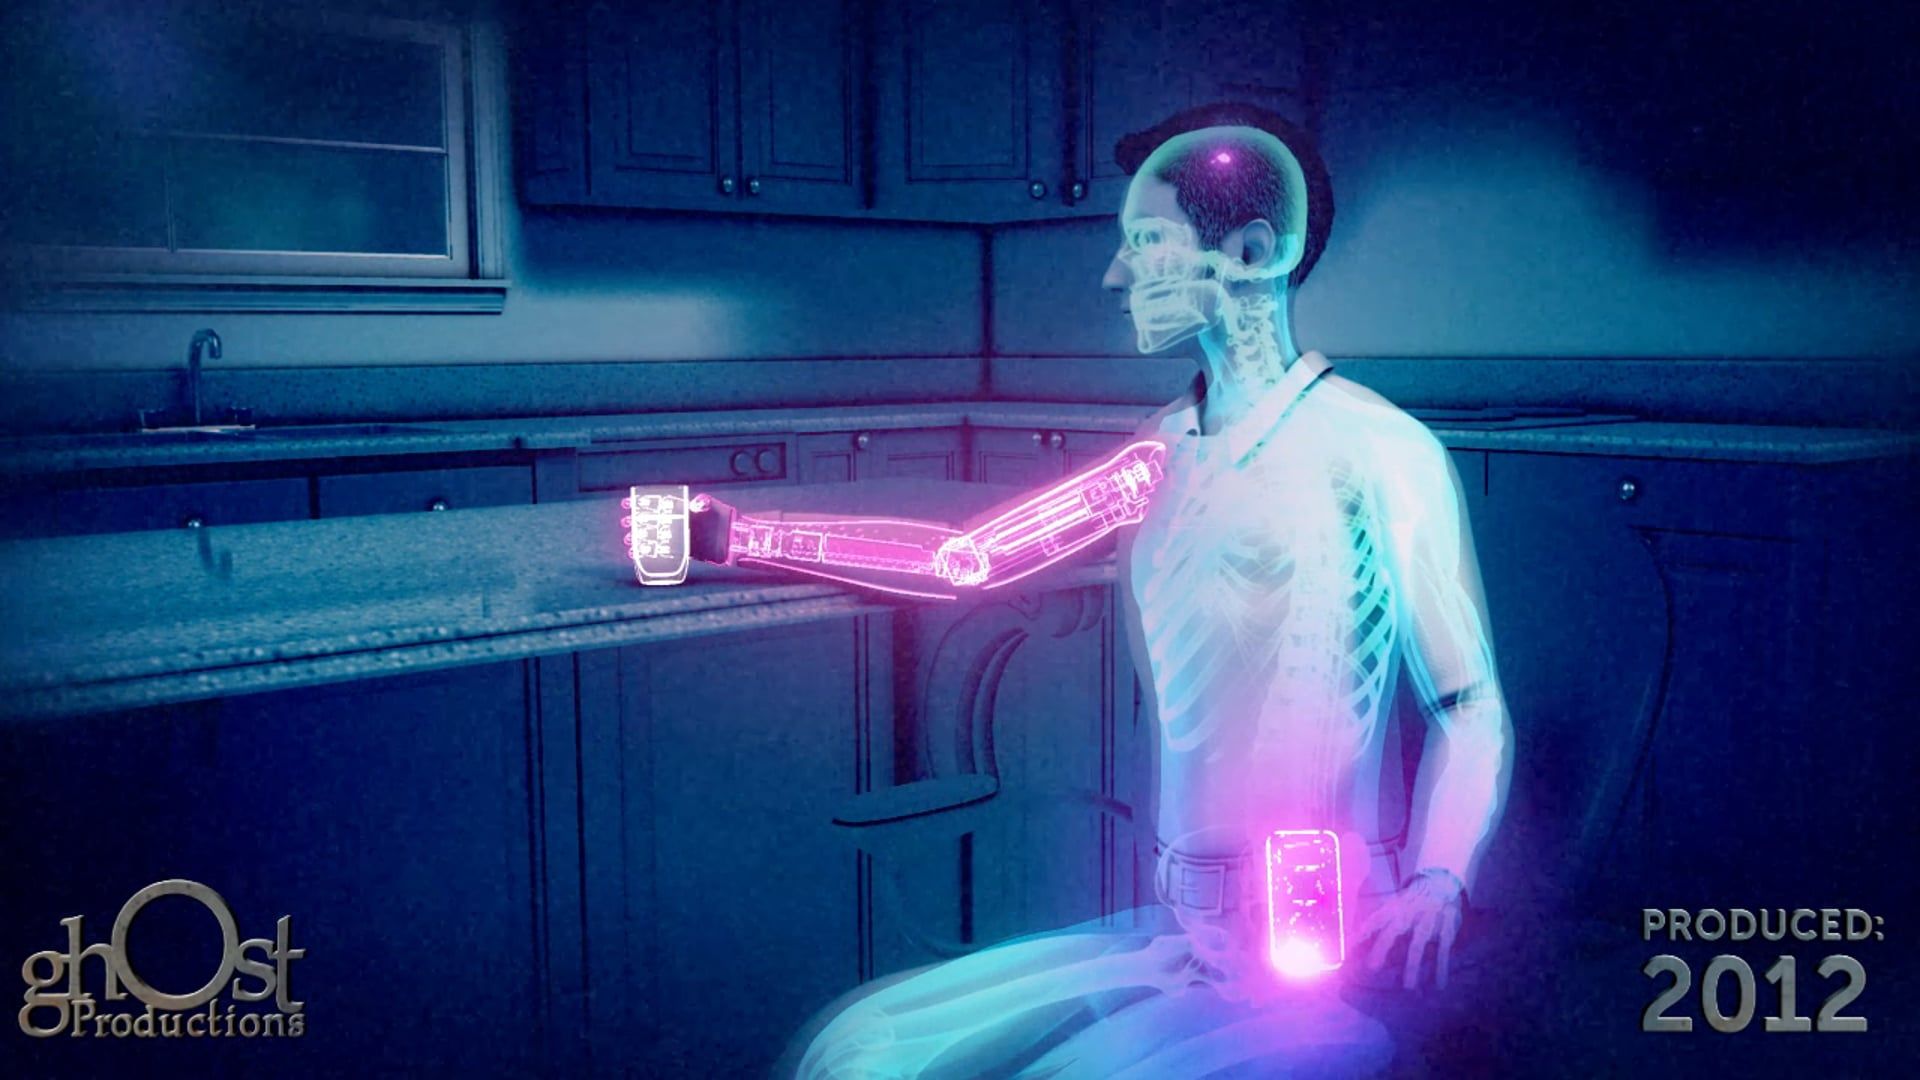

Medical Animation

Medical Devices